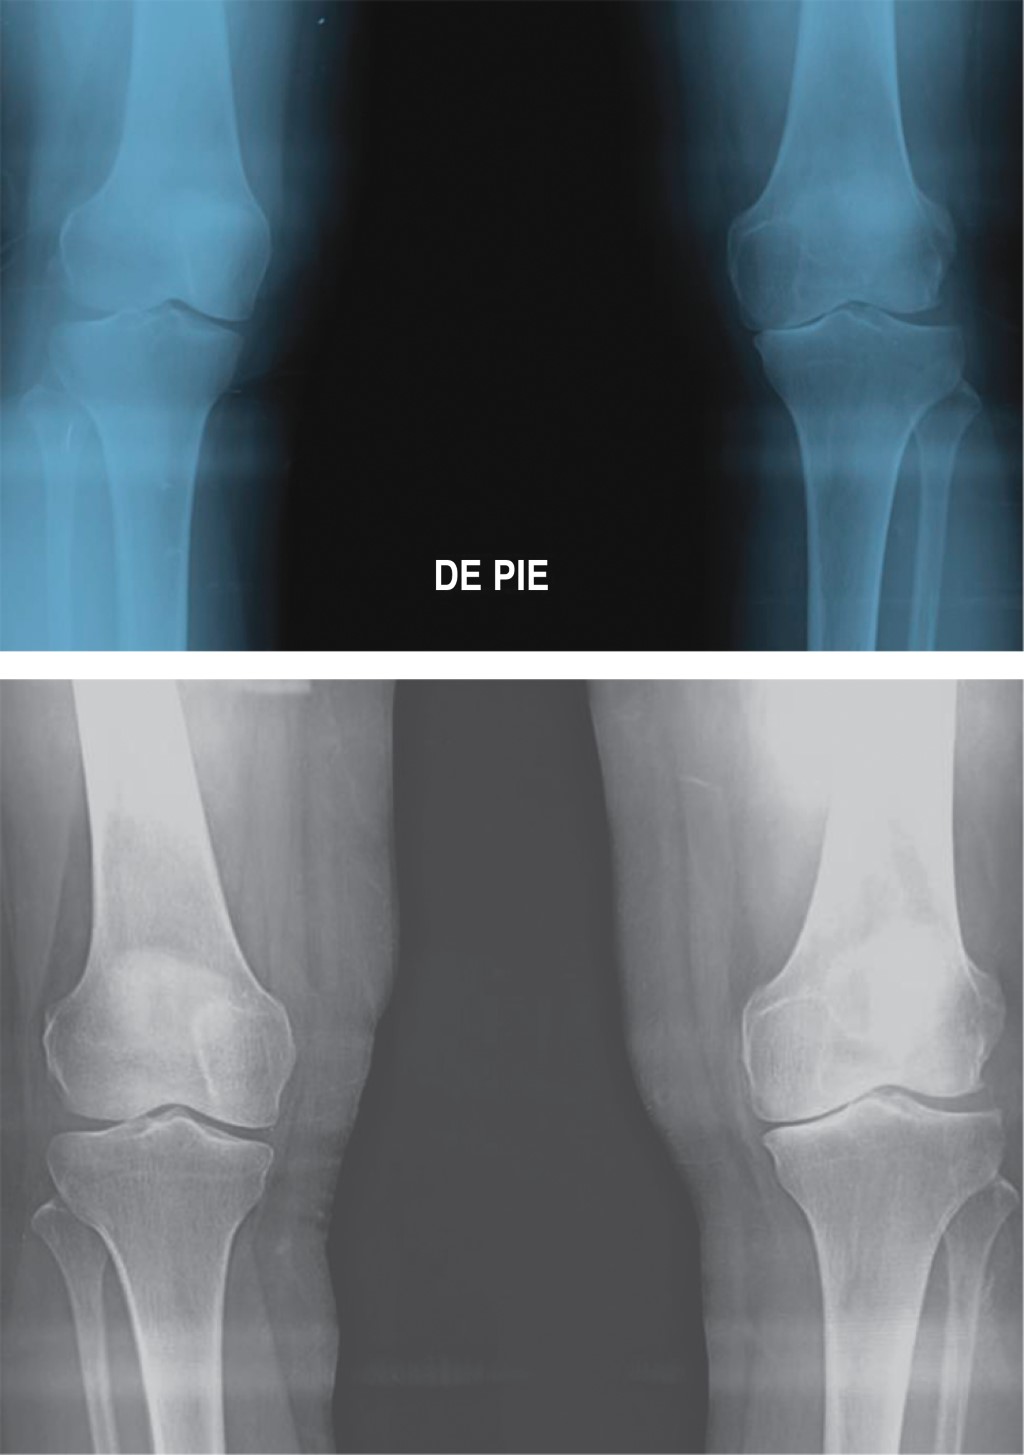

La radiografía simple continúa como la opción más económica para la detección y evaluación de la OA, permite la medición del espacio del compartimento medial y la alineación en varo o valgo. Para la evaluación radiográfica del eje de las extremidades inferiores, convencionalmente se solicita una telerradiografía o radiografía de extremidades inferiores como se le denomina hoy en día, que consiste en una exposición única, incluyendo desde las caderas hasta los tobillos con el foco distante, 1.80 metros del paciente, lo que disminuye errores de magnificación. Un estudio realizado por Kraus y colaboradores demostró una fuerte correlación entre los datos obtenidos en las mediciones de eje mecánico, mediante radiografías de toda la extremidad y las anteroposteriores de rodilla, las radiografías simples de rodilla son un método más fácil de obtener y evita la radiación a la pelvis, lo que las hace más apropiadas para evaluar el eje mecánico.8,9

La diafisectomía al peroné (DP) es una técnica quirúrgica novedosa para el tratamiento de la OA del compartimento medial de la rodilla y la deformidad en varo (Figura 1). Fue descrita por primera vez en 2015 en China, en donde se reporta que puede reducir significativamente el dolor de rodilla, mejorar el aspecto radiográfico, mejora la alineación en varo al aumentar el espacio articular medial y permite una recuperación funcional, proporcionando una mejoría en la movilidad de la articulación en cuestión; además, puede retrasar e incluso evitar la necesidad de una artroplastia total de rodilla; convirtiéndose además en una verdadera alternativa para para pacientes que, por sus comorbilidades o condiciones patológicas, el beneficio de colocar un reemplazo articular se vea superado por el elevado riesgo quirúrgico, ya que la diafisectomía es una cirugía simple y de breve tiempo quirúrgico.17,18 Comparado con la OTA, la DP tiene muchas ventajas, es una técnica quirúrgica simple y fácil de reproducir, es menos invasiva, demanda una incisión mínima, poca disección de los tejidos blandos y no se requiere de material ortopédico de fijación interna. El periodo de recuperación del postoperatorio también es menor que el de la OTA; asimismo, la DP está asociada con menos complicaciones. En cuanto a las desventajas de esta técnica en comparación con la OTA son la poca mejoría en casos con una angulación en varo de ≥15 grados, no se recomienda su uso en casos con artrosis postraumática y la posible lesión del nervio ciático poplíteo externo, que se ha reportado hasta en 1.8%, que se recupera totalmente entre tres y 10 meses posteriores a cirugía. También se ha reportado disminución de la fuerza de la extremidad intervenida hasta en 14.5%, que volvió a la normalidad dentro de las primeras cuatro semanas.18,19

En el periodo estudiado se identificaron 20 casos con diagnóstico de gonartrosis grado II-III de Kellgren-Lawrence y genu varo, los cuales fueron sometidos al procedimiento de DP. La edad media fue de 54 ± 6 años y 11 (55%) pacientes correspondieron al sexo femenino, el IMC fue 28.5 ± 3.4 kg/m2. Diez pacientes (50%) tuvieron gonartrosis derecha, el tiempo de evolución de la gonartrosis fue 19 ± 3 meses. El dolor preoperatorio fue de 7,6-8 la puntuación funcional del KSS fue 45 (40-49) y del WOMAC fue de 59 ± 7. Radiográficamente la altura del espacio articular medial fue de 2.2 ± 0.6 milímetros, el espacio articular lateral fue de 7.8 ± 1.9 milímetros y la proporción del espacio articular fue 0.31 ± 0.15 milímetros. El eje de la extremidad inferior de acuerdo al ángulo femoro-tibial fue 174 ± 1 grados y de acuerdo al ángulo cóndilo-meseta de 6.15 ± 1.34 grados.

Radiográficos: la altura del espacio articular medial (EAM) se amplía al realizar DP, la mejoría del espacio se mantiene hasta después de 24 meses de realizada la cirugía (2.2 ± 0.6 vs 2.5 ± 0.5 mm, prequirúrgica y a los 24 meses respectivamente; p = 0.004) mientras que la altura del EAL se reduce significativamente desde el postquirúrgico inmediato (7.8 ± 2.0 vs 4.0 ± 0.8mm, prequirúrgico y postquirúrgico respectivamente; p ≤ 0.001) y se mantiene así a lo largo de 24 meses (4.0 ± 0.8 mm vs 4.1 ± 0.8 mm, postquirúrgico y 24 meses respectivamente; p = NS).

La proporción del espacio articular (PEA) se incrementa después de realizar la DP progresivamente desde el postquirúrgico inmediato (0.57 ± 0.14 vs 0.31 ± 0.15, postquirúrgico y prequirúrgico respectivamente; p ≤ 0.001) hasta los 24 meses posteriores a la cirugía (0.61 ± 0.12 vs 0.57 ± 0.14, 24 meses y postquirúrgico respectivamente; p ≤ 0.001) (Tabla 4). Se corrigió la alineación en varo de la extremidad inferior tomando en cuenta el ángulo femoro-tibial (AFT) inmediatamente después de la DP (178 ± 1 vs 174 ± 1 grados, postquirúrgica vs prequirúrgico respectivamente, p ≤ 0.001) y se mantuvo así a lo largo de los 24 meses de seguimiento (177 ± 1 vs 178 ± 1 grados, 24 meses y postquirúrgico respectivamente, p = NS).

El ángulo cóndilo-meseta (ACM) disminuyó de manera significativa desde el postquirúrgico inmediato (5 ± 1 vs 6 ± 1 grados, postquirúrgico y prequirúrgico respectivamente; p ≤ 0.001) sin cambios a los 24 meses del seguimiento (5 ± 1 vs 5.3 ± 1 grados, postquirúrgico y 24 meses respectivamente; p = NS) (Tabla 4).

Radiográficamente la altura del EAM aumentó hacia el final del estudio y la altura del EAL disminuyó desde el postquirúrgico inmediato, mientras que la PEA mejoró desde el postoperatorio inmediato y se mantuvo durante los 24 meses de seguimiento. Como se ha observado en otros, la altura ganada en el espacio articular medial no es proporcional a la disminución del espacio articular lateral. Estudios biomecánicos han demostrado que la DP consigue disminuir la presión en el compartimento medial de la rodilla hasta en 21.57%, mientras que la presión del compartimento lateral incrementa sólo 12.92%, describiendo entonces que la presión total sobre la articulación de la rodilla disminuye después de la DP.18 Al igual que ha sido reportado por Qin D y colaboradores, Yang y su equipo y Utomo y su grupo, observamos que el AFT y el ACM mejoraron en el postquirúrgico inmediato en 100% de los pacientes y, por lo tanto, también la angulación en varo de la extremidad afectada, a los 24 meses de seguimiento sólo hubo regresión hacia el varo en promedio de un grado.2,23-25